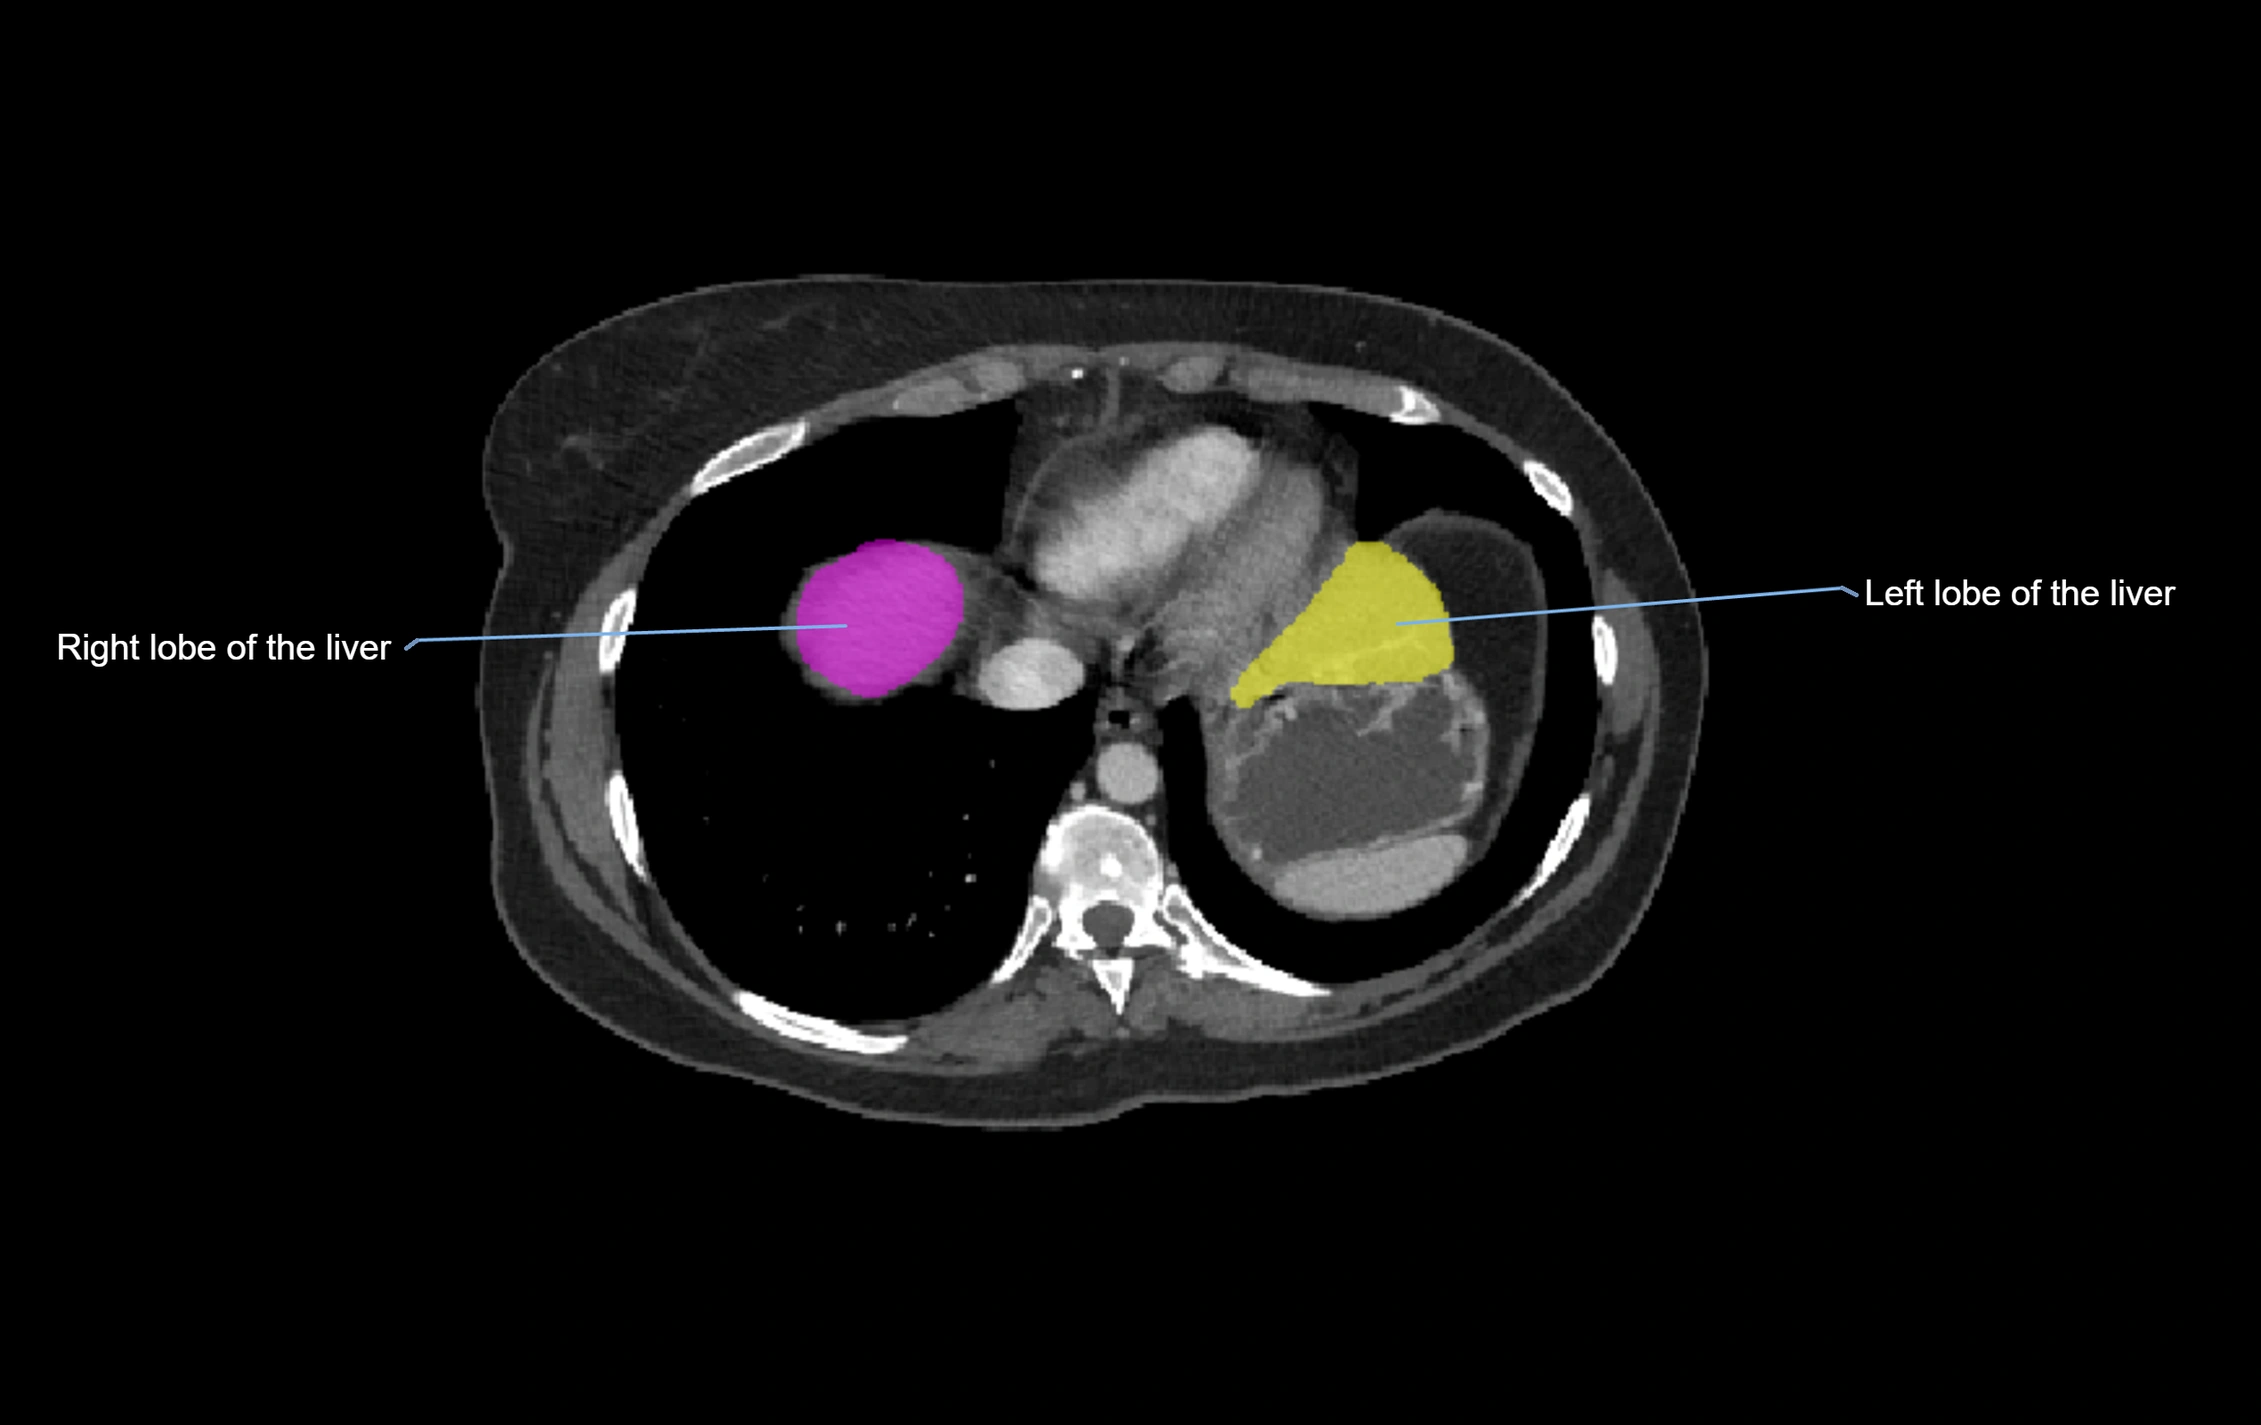

MRI image

image